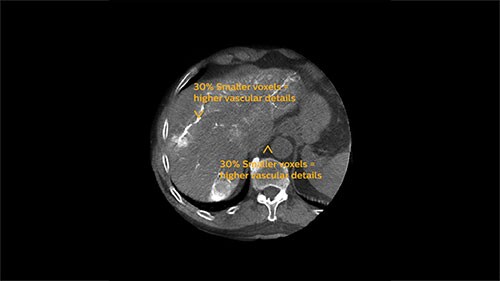

Step 3 – Assess

5 sec. Fast acquisition = reduces breathing artifacts

At the end of each procedure the dedicated oncologic imaging of XperCT Dual helps to determine the treatment endpoint in TACE for HCC.⁵ With XperCT Dual’s fast acquisition protocol, high resolution and soft-tissue contrast, a study has shown that its dual phase image information even correlates with the tumor response in the one-month follow-up MRI.⁶